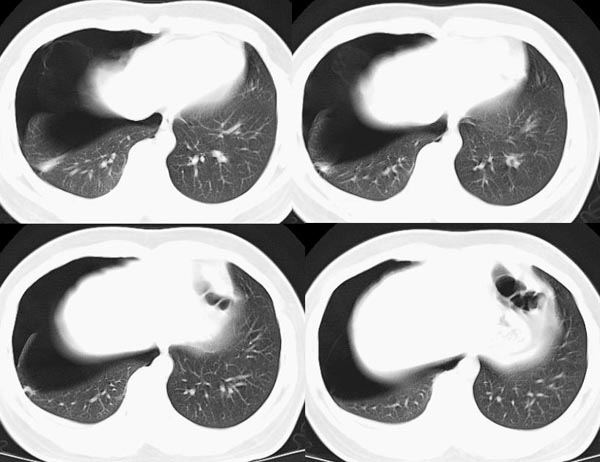

m21y既往体健,否认结核、支扩等病史;1周前患上感,无明显咳嗽,自觉无明显不适。单位体检透视时发现右侧液气胸!cr及ct如下(肺组织窗:l:-598hu w:1132hu):请大家会诊!!

右侧巨大含气囊性病变,壁薄、光整、其外侧见气体。右肺压迫性肺不张、胸腔内见少量积液。纵隔向左侧移位。左肺未见异常。诊断:1.右侧含气肺囊肿(先天性)。2.右侧液气胸。(少量液体)3.右肺压迫性肺不张。我也遇见一例这样的病人。女性。股骨外伤就诊。常规胸片发现右侧囊性病变。